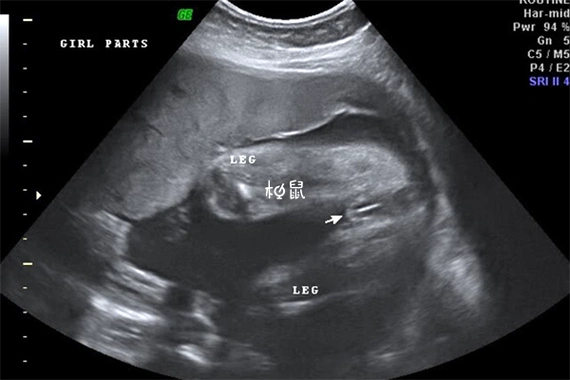

b超男宝三条线和女宝三条线对比图来了!学会自己就能做判断